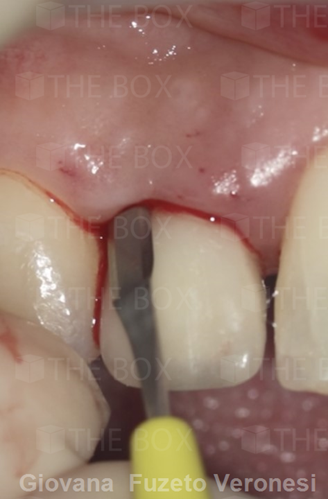

Infra bony defect one wall defect follow up 18 months show regeneration of buccal bone and interdental defect utilizing allograft bone substitute